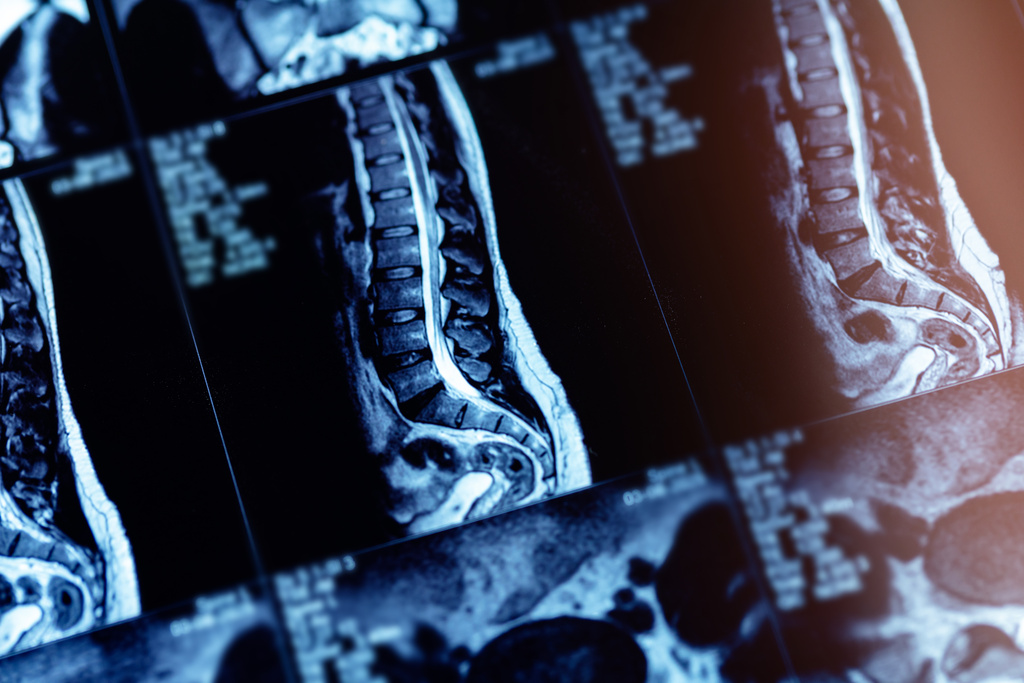

Bevor wir mit der Behandlung beginnen, führen wir eine sorgfältige Diagnostik mittels Röntgen, und MRT durch. So können wir die genaue Ursache der Schmerzen bestimmen und die passende Injektionstechnik auswählen. Die Injektionen erfolgen unter bildgebender Kontrolle um höchste Präzision und Sicherheit zu gewährleisten. Dadurch werden Risiken und Nebenwirkungen minimiert und die bestmögliche Wirksamkeit erzielt.